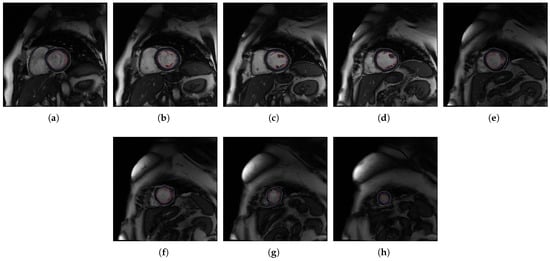

2. Methods

2.1. A Software Tool to Quantify the Trabeculae Degree in the LV Myocardium for a Population of Patients with Genetic Cardiomyopathies (QLVTHCI)

- The different MSERs are detected in a centered ROI of each input image by the use of OpenCV [23]. As the LV cavity is normally represented by a circular shape, the centroid of each MSER detected is computed in order to automatically identify the left ventricle cavity anywhere in the image and for applying the convex hull.

- The previous application of the convex hull allows a second refining to optimize the search process of the external layer and the trabeculae areas. The parameter e-expand is redefined and adjusted to accurately determine the external layer of the compact zone, thanks to plotting several lines from the centroid of the LV to reach the points of the external layer. This parameter establishes the distance of the lines between the centroid of the LV cavity and the possible space where the external layer can be found, taking into account the particular features of genetic cardiomyopathies. We optimized the parameter e-expand for different situations or possible cardiomyopathies.